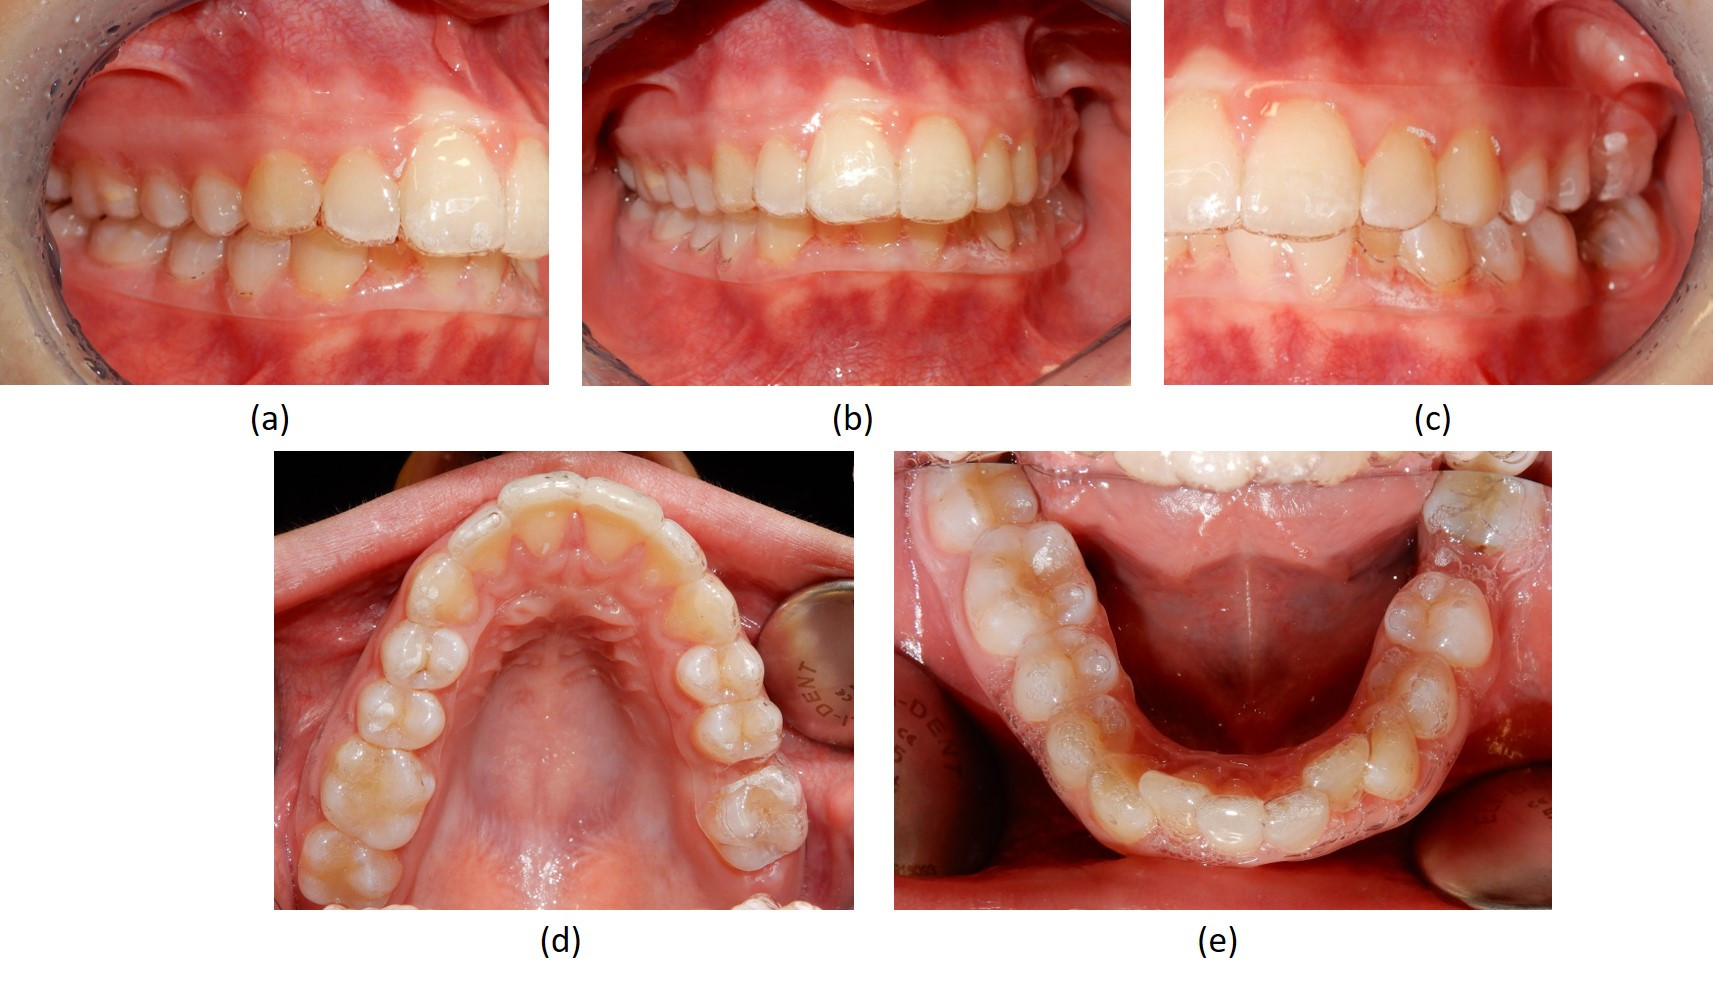

Fotografie intraorali post-trattamento

Fig. 6 Fotografie intraorali post-trattamento. (a-c) Immagini che mostrano l'occlusione finale; (d) spazio estrattivo superiore chiuso sul lato sinistro per mesializzazione del secondo molare nello spazio del primo molare mancante; (e) inferiormente rimane una lieve mesio-rotazione  del secondo molare inferiore sinistro, ortodonticamente trasposto nello spazio del primo molare mancante, ma lo spazio estrattivo è stato chiuso in modo efficiente